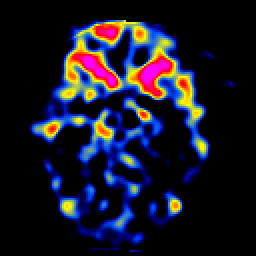

SPECT TL Study #5 -- Slice #22